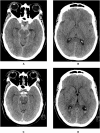

Introduction: The diagnosis perimesencephalic subarachnoid hemorrhage (PMSAH) is based on a specific distribution pattern within 72 h after ictus. However solid evidence is lacking for this time window with the potential risk that blood distribution can change over time, with implications for the management of these patients.

Research question: To study cisternal and intraventricular blood pattern changes on initial and follow-up non-contrast CT scans (NCCTs) during the first 72 h.

Materials and methods: This retrospective study included consecutive PMSAH and non-perimesencephalic (NPSAH) patients in whom at least two NCCTs were performed within the first 72 h. Presence and changes in the distribution of cisternal and intraventricular blood was independently assessed by three observers.

Results: 135 patients (62 PMSAH and 73 NPSAH) were included. The distribution of SAH remained unchanged within the first 72-h in 63 (47 %) patients (PMSAH: 38 (61 %), NPSAH: 25 (39 %))(p < 0.01). An increase in SAH distribution from 0 to 6 h was seen in 7/47 PMSAH (15 %) versus 24/47 (51 %) in NPSAH patients (p < 0.01). A decrease in SAH distribution from 0 to 6 h was seen in 6/47 (13 %) PMSAH patients versus 2/47 (4 %) NPSAH patients (p < 0.01). Between 6 and 24 h, a 72 % decrease (10/14) was only seen in NPSAH patients. The diagnosis PMSAH never changed to NPSAH or vice versa due to SAH redistribution.

Discussion and conclusion: Within the first 72 h after ictus, redistribution of cisternal and intraventricular blood is seen more often in NPSAH than in PMSAH patients but did not change the specific diagnosis.